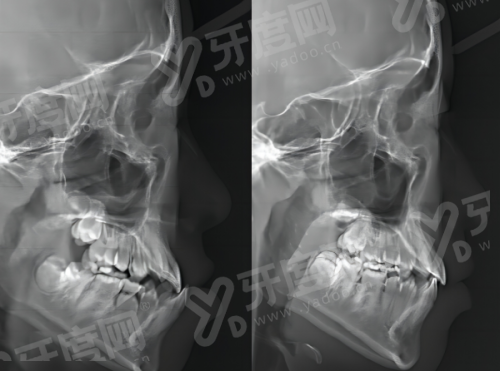

1、 首先通过CBCT影像、口腔扫描获取患者口腔软硬组织三维数据,全方面了解牙槽骨形态、骨量、咬合关系等口腔细节信息。

1、 完成口腔CBCT扫描、口内扫描取模,获取牙槽骨形态、骨量、咬合关系等全维度口腔数据,全方面掌握患者口腔状况。